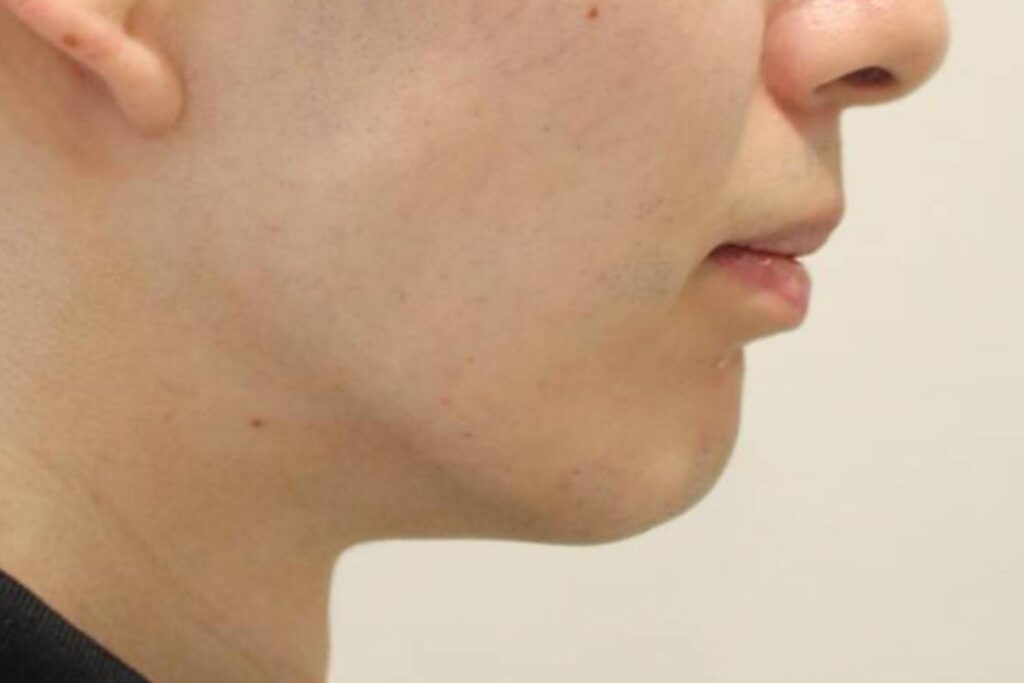

上顎前突(case 3)

出っ歯を治したい(ワイヤー矯正)

前歯のでこぼこと、出っ歯を治したいということで矯正治療を行いました。

Before